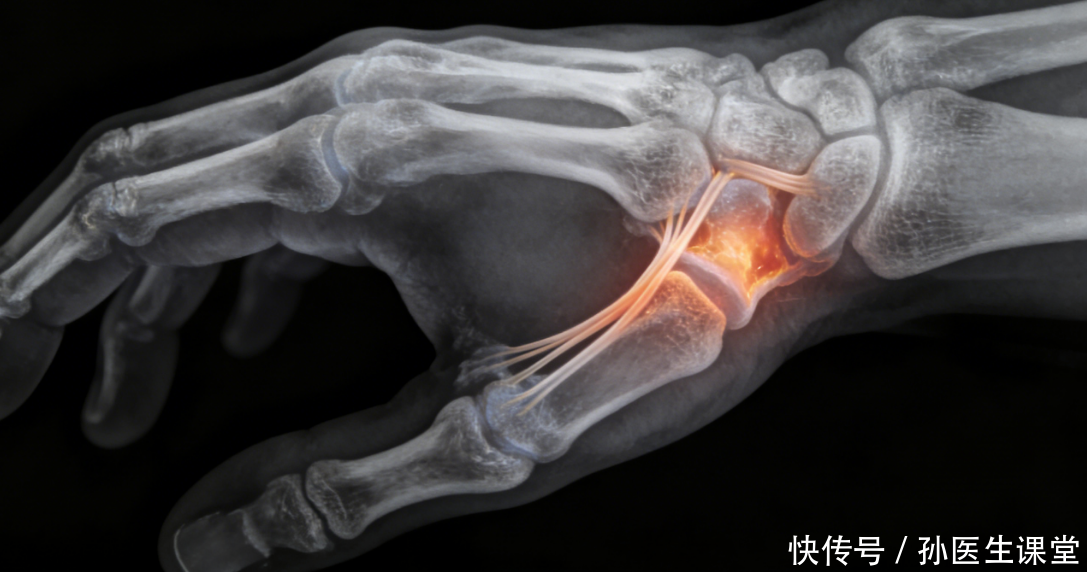

当先,咱们得先搞昭着,腱鞘炎到底是个啥。可能有东说念主一听到“炎症”就以为是细菌感染,其实否则,腱鞘炎大多是“劳损出来的病”。不妨将手腕与手指间的肌腱,遐思成一根“绳索”。而那牢牢包裹着肌腱的腱鞘,恰似一层经心呵护的“防护套”,缄默看护着肌腱的泛泛运作。这层保护套会分泌若干滑液,恰似为“绳索”涂抹了润滑油,使肌腱得以顺畅地往复滑动。正因如斯,咱们的手腕与手指方能活泼闲静地行动。

可如果这根“绳索”被过度使用,比如永劫辰反复摩擦、拉伸,不祥被失当受力挤压,那层“保护套”就会受到毁伤。就像咱们反复弯折一根电线,外层的胶皮会沉静磨损、变厚、变硬一样,腱鞘受损后会出现充血、水肿,进而增生、肥厚,致使变得褊狭。这么一来,“绳索”在“保护套”里滑动时就会变得卡顿、不顺畅,每动一下都会产生摩擦和祸患,严重的时刻,手指或手腕致使会“卡住”,无法泛泛迤逦或伸直,这等于咱们说的腱鞘炎。